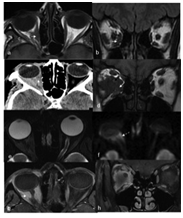

Her magnetic resonance imaging (MRI) at presentation Figure 1A&B showed right small soft tissue mass between the optic nerve and the medial rectus muscle. Further imaging studies by computed tomography (CT) and MRI showed significantly enlarging orbital lesion over one year (Figure 1C−H). However, there was no extension to the brain.

Figure 1 (A-H): Initial Magnetic Resonance (a: Axial and b: Coronal T1-weighted Images) in 2013 showing a small soft tissue mass between the optic nerve and the medial rectus muscle (white arrow). (2C) Non contrast Computerized Tomography (CT) scan done in 2014 showing significant increase in the size of the lesion filling the RT retro-bulbar area. (2D−H) coronal T1, Axial T2, the retro-bulbar area infiltration with restricted pattern of the lesion on Diffusion-weighted MRI image (f) indicating high degree of cellularity, malignancy (white dashed arrow)with intense enhancing pattern on post contrast fat suppressed images that encircling the optic nerve which appears as a black dot against the whitish diffusely enhancing mass (G−H).